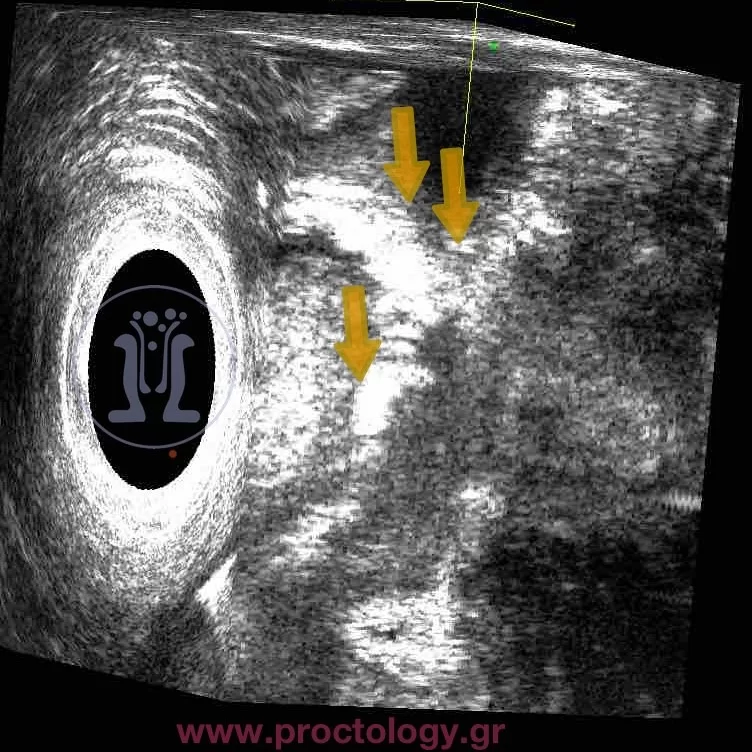

Περίπτωση ασθενούς με ακράτεια στα αέρια και συρίγγιο μετά από εγχείρηση νεαροποίησης ραγάδας με laser. Φαίνεται σαφώς το στόμιο του συριγγίου και στο ενδοπρωκτικό υπερηχογράφημα … Περισσότερα

Περιεδρικό συρίγγιο με ακράτεια στα αέρια σαν επιπλοκή νεαροποίησης ραγάδας με laser. Οπίσθια έσω σφιγκτηροτομή ολικού μήκους- keyhole deformity